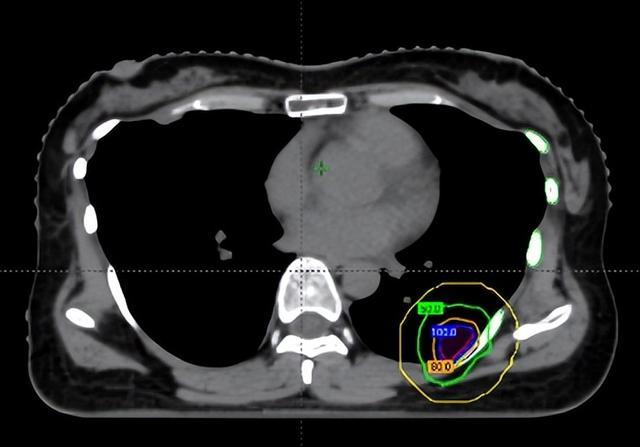

在维持前,团队通过四维CT对三个病灶进行精确定位,尤其是紧贴肋骨的阿谁病灶,连与肋骨之间极其微弱的裂缝齐被明晰标注出来。

随后参加最中枢的剂量狡计局势。胡英评释注解与李忠伟、雷大明物理师反复推演射澄清径和强度分散,把高剂量区域严格戒指在肿瘤鸿沟内,同期让剂量在极短距离内飞速下跌。不错清醒为,快乐飞艇在体内完成了一次“毫米级雕塑”:肿瘤被精确遮盖,而近在目前的肋骨却被保护在安全鸿沟内。